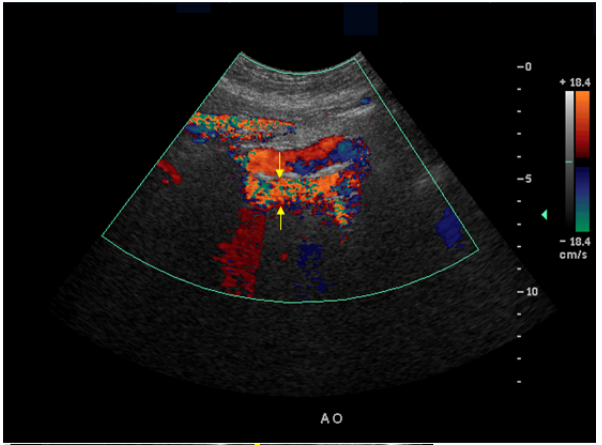

61.70歲女性病人,因腹痛就診。超音波檢查時發現腹主動脈(矢狀切面)有異常如下圖,箭號所指最可能的 假影為何?

(A)側葉假影(side lobe artifact) (B)鏡像假影(mirror image artifact) (C)反褶效應假影(aliasing artifact) (D)回音增強現象(acoustic enhancement)